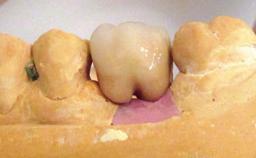

Peri-implant Carcinoma

Maximilian Moergel, Peer Wolfgang Kämmerer, Bilal Al-Nawas

Oral implants are highly successful and offer long-term benefits, especially in the rehabilitation of edentulous patients or patients with oral defects following ablative tumor surgery (Albrektsson and coworkers 1986), and also after radiation therapy (Schiegnitz and coworkers 2014). With the number of implants placed globally going into the millions, implant dentists have observed some rare adverse events. Although carcinogenesis around implants is an exceedingly rare phenomenon, we recently reported about 15 patients treated for carcinomas adjacent to implants at our clinical department over a period of fifteen years (Moergel and coworkers 2014). The following case represents a patient of this cohort; it discusses possible risk factors and makes suggestions for a recall schedule. A 70-year-old woman was referred to our outpatient department for evaluation of a rapidly growing macroscopic alteration of the mucosa in the left mandible.